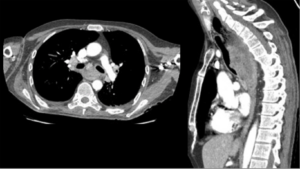

TC de tórax con contraste i.v